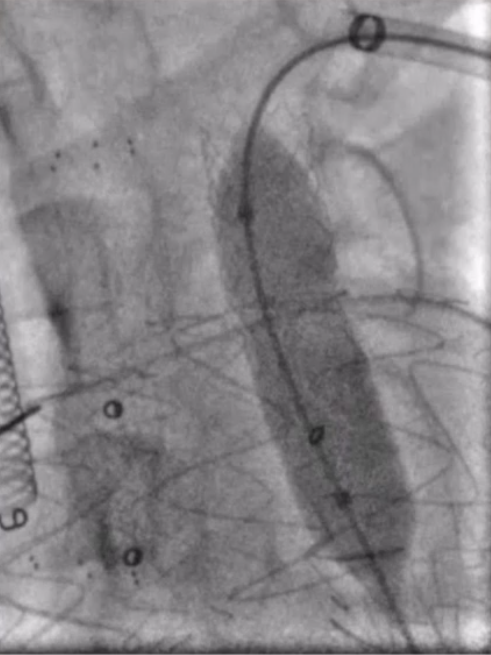

将支架送入覆膜区约1cm释放支架。之后,更换更大口径的球囊送至主动脉弓内进行后扩张,使支架呈喇叭口状,以稳定两者结构,减少内漏的发生。由于左锁骨下动脉位于假性动脉瘤的破口位置,此处使用球扩覆膜支架实现了更加精准的定位,有效降低了内漏风险。

球囊回收时

带鞘进开窗口

置入VBX11-29mm支架,支架伸入

覆膜支架约1cm后释放并球扩塑形

★ 术后造影

支架释放完毕后,分别进行左前斜和右前斜造影。结果显示,支架形态良好,左侧颈总动脉和左锁骨下动脉分支血流通畅。右前斜位可见假性动脉瘤封闭完全,仅有少量内漏,考虑与膜渗相关。同时行颅内动脉造影,结果显示双侧颈动脉、双侧椎动脉以及颅内血管显影良好。结果表明,手术成功实现血管重建,假性动脉瘤有效封堵,且未对脑部供血造成不良影响。